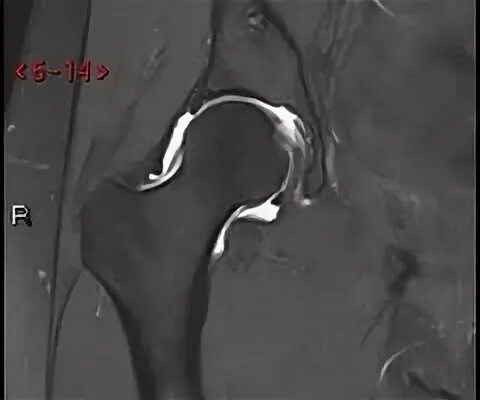

Мрт тазобедренного сустава в минске